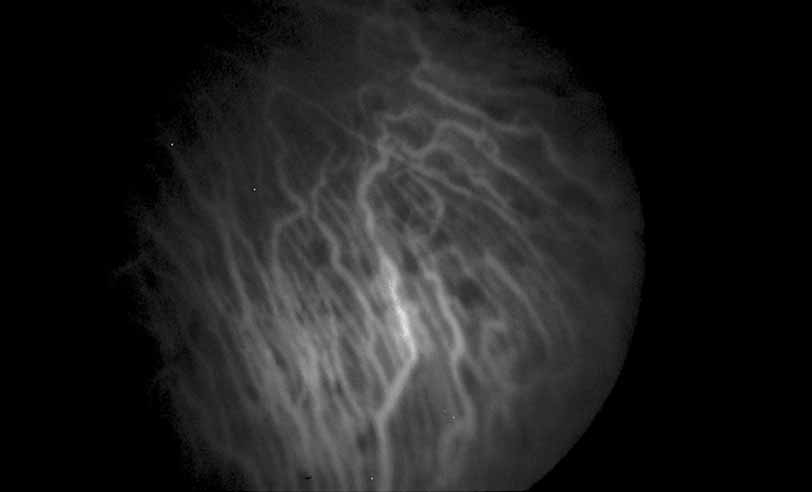

Fig. 28 Serpiginous choroiditis. ICG angiography early frame shows multiple hypofluorescent spots in the location of the lesions seen on color photography.

Fig. 29 Serpiginous choroiditis. ICG angiography later frame shows multiple hypofluorescent spots in the location of the lesions seen on color photography.

A number of inflammatory diseases of the posterior segment produce changes in the retinal pigment epithelium, which may range from the relatively subtle alterations in multiple evanescent white dot syndrome (see Figs. 22 and 23)79 to the striking opacification and pigment spotting of acute multifocal placoid pigment epitheliopathy (see Figs. 24 and 25),80–85 serpiginous choroiditis(see Figs. 26, 27, 28, and 29),22–30 and luetic neuroretinitis (see Fig. 9).16–21 In fact, there has been some controversy in the interpretation of the angiographic features of these diseases based on the distinction between hypofluorescence of the choroidal vasculature because of presumed vasculitic nonperfusion and simply optical blockage because of primary inflammation and opacification of the overlying retinal pigment epithelium. ICG angiographic findings in these disorders would favor choroidal hypoperfusion in many of these instances since ICG fluorescence is unlikely to be blocked by subtle changes in the overlying pigment epithelium.